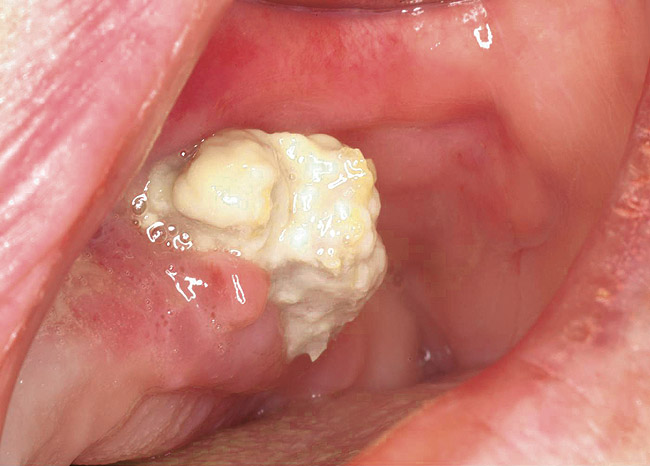

Figure 14  Spontaneous BRONJ.

Figure 14

Figure 15  Removal of the necrotic bone material.

Figure 15

Figure 16  Necrotic bone.

Figure 16

As stated earlier, spontaneous osteonecrosis is also possible. Figure 14 shows a case of spontaneous BRONJ resulting from wearing an ill-fitting denture. The patient had noticed the foreign material, but chose not to act on it. When the material was removed in the dental office (Figure 15 and Figure 16), blood streamed from the nose so severely that the patient had to be sent to an ear, nose, and throat (ENT) physician. The ENT took a computed tomography scan, which showed a large radiolucency in the upper left quadrant where the foreign material once had been (Figure 17). A review of the radiograph (Figure 18) showed that bone in the maxillary arch had decreased mineral density compared with the mandible. The biopsy report found necrotic bone with organisms consistent with actinomyces. These findings were consistent with biopsies found in the literature.22 When the patient returned for a 1-week follow-up, she still had signs of infection and the site had a foul odor and a discharge (Figure 19). The patient was informed that she should follow up with the ENT and return to the dental office after the infection had been resolved.